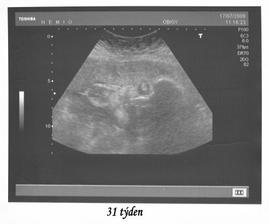

so.19.9.2009 40tt narodil se nám chlapeček Honzík v 11:25 hod. vážil 3900 g a měřil 53 cm